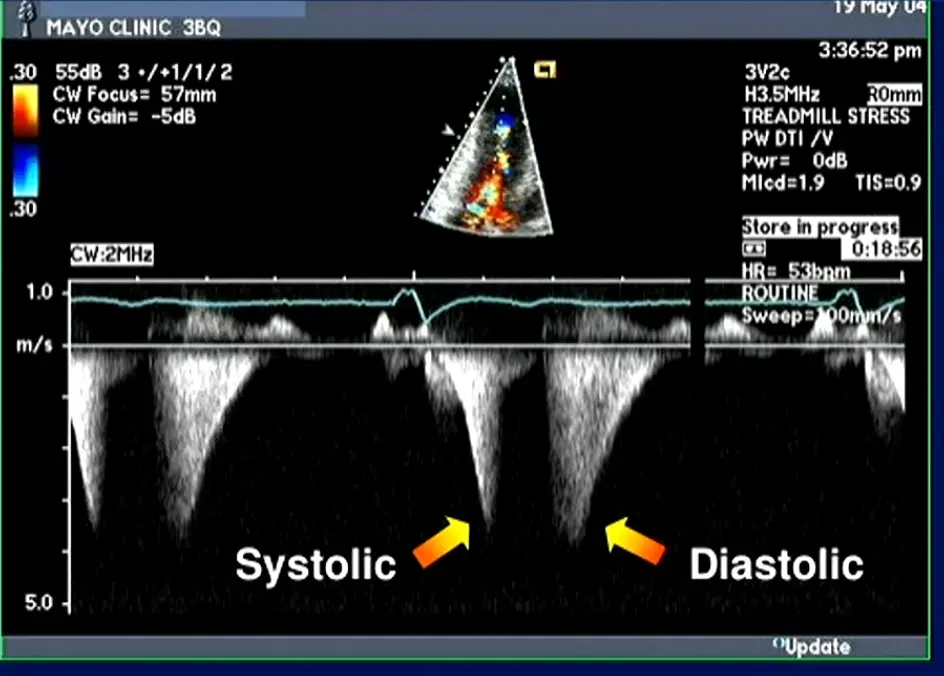

Pulsed Wave Doppler of the thoracic aorta

- Double-peaked, “spike-and-dome” pattern

-

Aortic pressure tracing will also feature the “spike-and-dome” pattern

- M-mode in the parasternal long-axis view may assess for midsystolic notching of the aortic valve, reflecting very rapid ejection of LV stroke volume in early systole followed by attenuation of stroke volume in the obstructive phase.